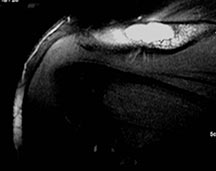

Radiographic Presentation